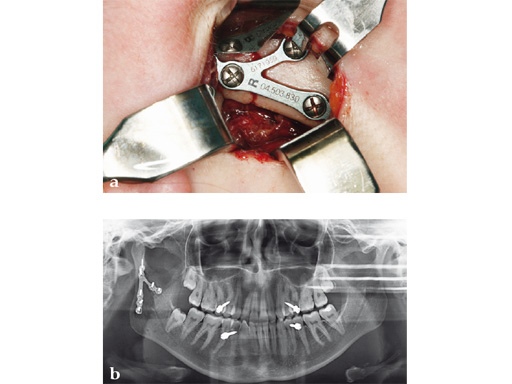

Case 3

Case provided by Carl-Peter Cornelius, Mnchen, Germany